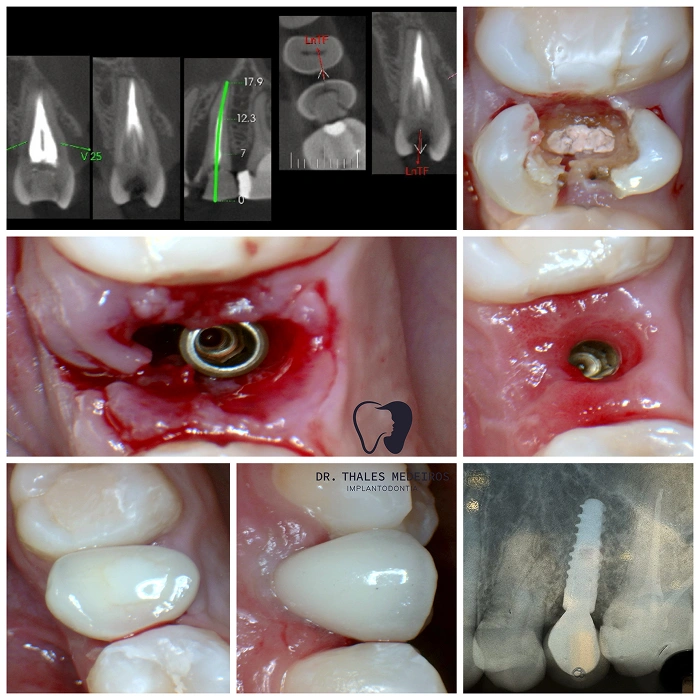

Implantes Dentários: Sorrisos restaurados com segurança e precisão

Recupere seu sorriso e sua qualidade de vida com os implantes dentários do Dr. Thales Medeiros. Com 9 anos de experiência e quase 2.000 implantes realizados, ele é referência na Paraíba em reabilitação oral. Os implantes proporcionam benefícios como restauração da mastigação, preservação da estrutura óssea, estabilidade dentária duradoura, melhora da estética do sorriso e aumento da autoestima.

Cada procedimento é planejado de forma personalizada, unindo tecnologia de ponta e cuidado humanizado para oferecer resultados seguros e naturais.

Já são quase 2.000 implantes realizados: segurança, conforto e resultados naturais para seu sorriso.